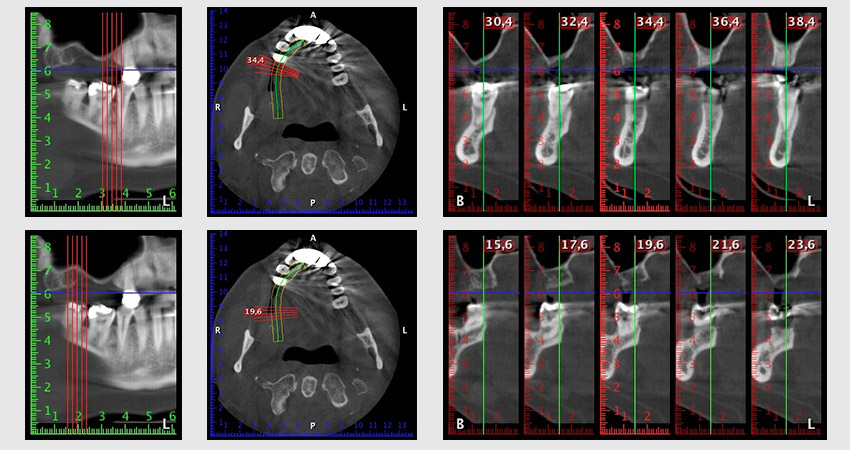

To restrict the augmentation to region 14, and in consultation with the patient, it was planned that implant 16 would be placed, inclined, in the dorso-cranial direction (Fig. 8).

This method requires a screw-retained solution for the final restoration. An angled abutment (e.g. 35°) was required so the screw could be perpendicular to the occlusion plane, which allowed the bridge to be attached occlusally.

Image 8: DVT with plan of insertion angle for implant 16